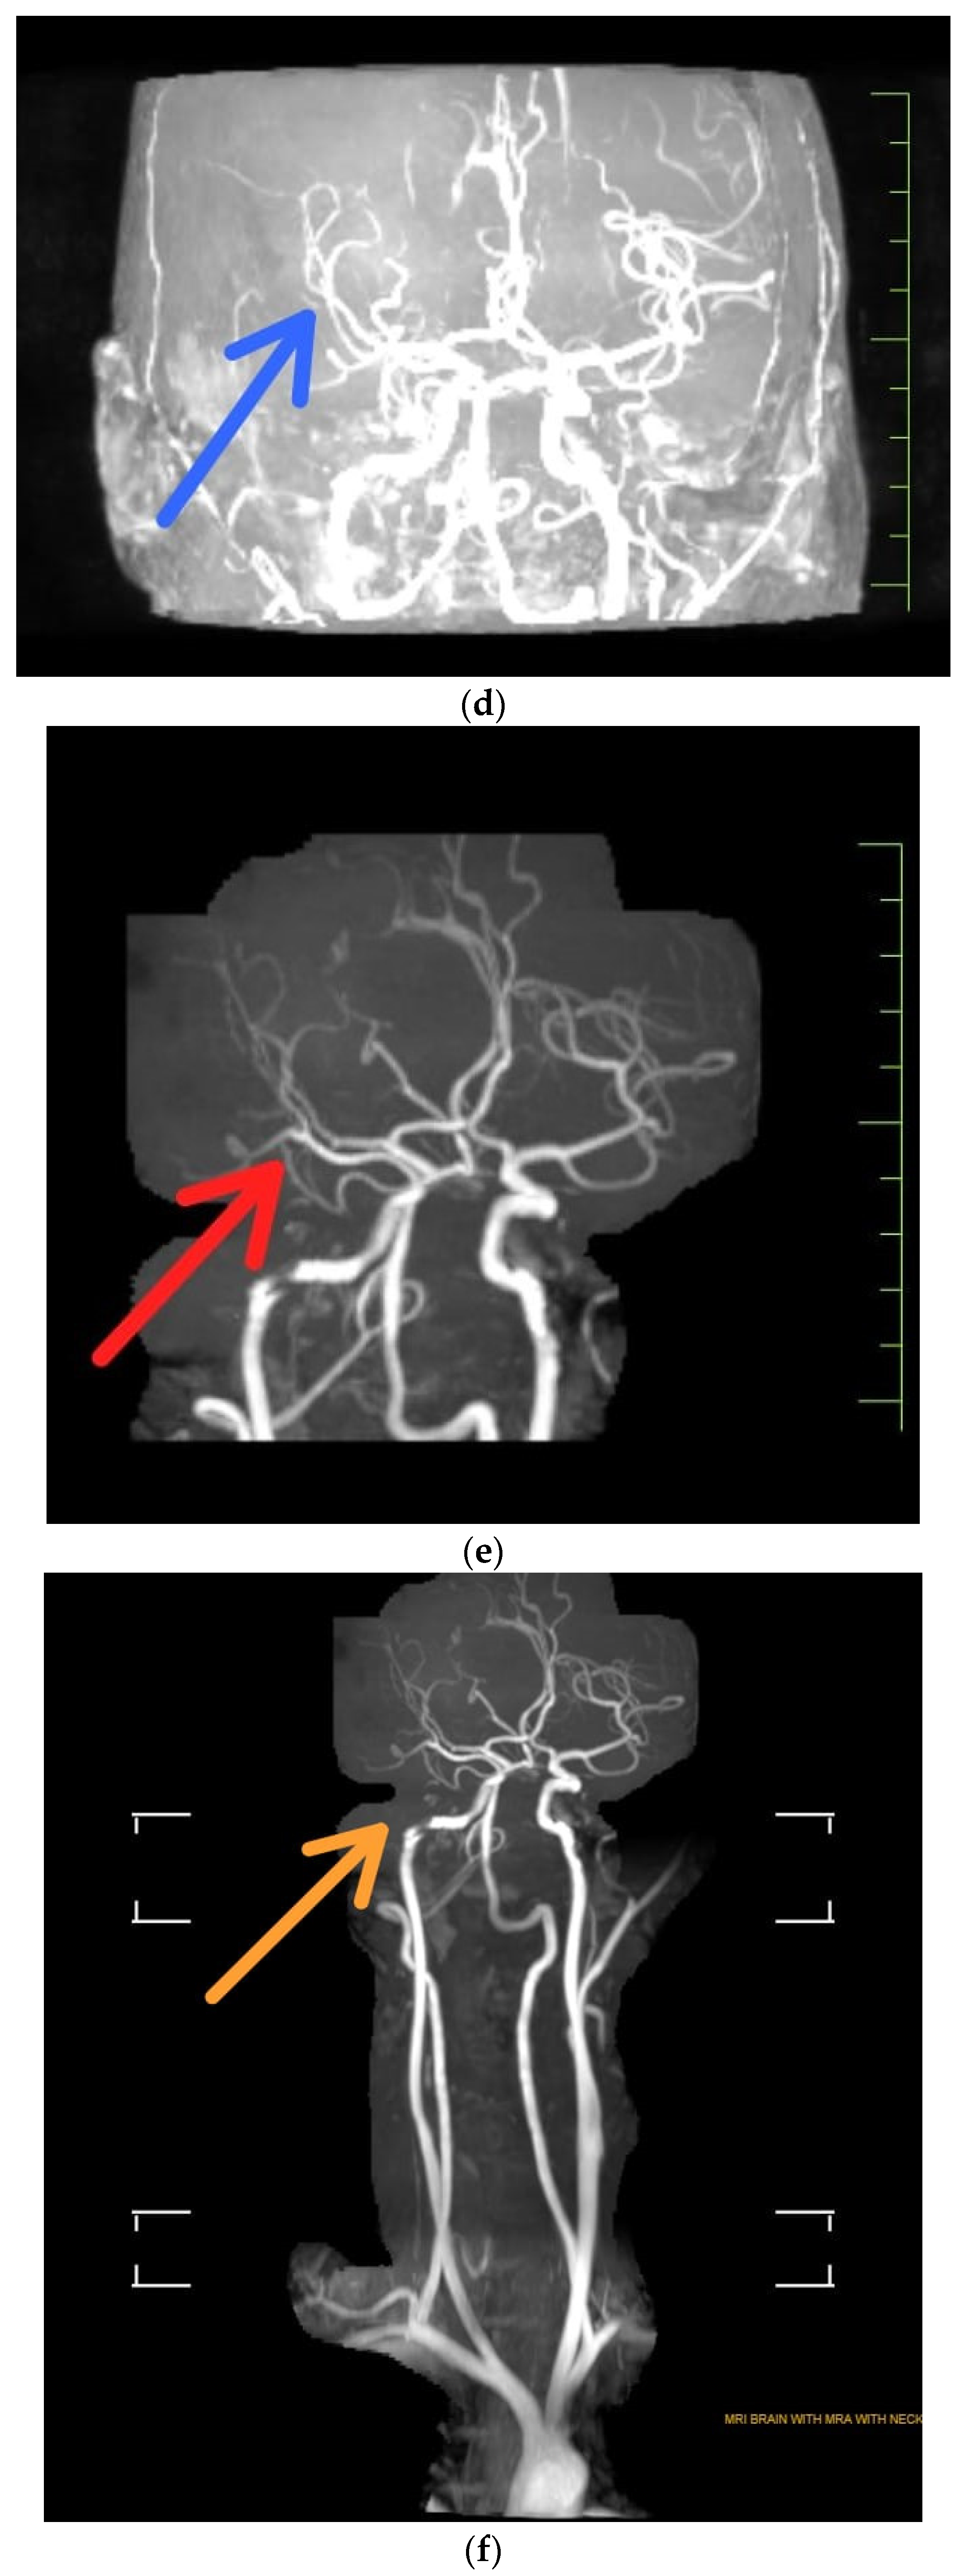

- (a)

- T2 Weighted MRI unveiling Encephalomalacia with surrounding gliosis in right parieto-temporal lobe with green arrow

- (b)

- Coronal T2 weighted indicating Stage 3 Wallerian degeneration with purple arrow where Gliosis replaces the degenerating axons and myelin sheaths, and myelin lipid breakdown (more than 14 weeks). Gliosis appears as an area with increased T2/FLAIR signal, somewhat reduced T1 signal. Light blue arrow indicates Encephalomalacia with surrounding gliosis noted in right parieto-temporal lobe.

- (c)

- T2 FLAIR (Fluid Attenuated Inversion Recovery) indicated atrophy of right middle cerebral peduncle s/o Wallerian degeneration [7].